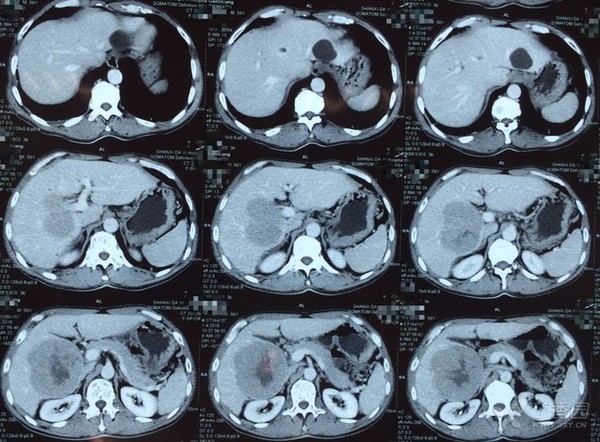

图 2 彩超

彩超诊断意见:肝实性低回声占位,考虑肝癌,肝囊肿。